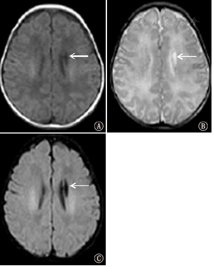

出血急性期MRI表现为T1WI等信号或稍低信号、T2WI高信号;亚急性早期呈T1WI高信号,T2WI稍低信号,亚急性晚期呈T1WI和T2WI高信号。在SWI序列上呈明显低信号(图2)。

注:A:左侧侧脑室内小团状T1WI稍高信号;B:左侧侧脑室小团状T2WI低信号;C:磁敏感加权成像上左侧侧脑室低信号磁敏感灶,范围较常规平扫增大,另外右侧颞叶皮质见点状微出血灶,常规平扫未显示 A:T1-weighted magnetic resonance image showed small clusters slightly increased signal intensity in the left lateral ventricle; B:T2-weighted magnetic resonance image showed decreased signal intensity in the left lateral ventricle;C:susceptibility weighted imaging showed decreased signal intensity magnetic susceptibility focus in the left lateral ventricle, to compare with the conventional magnetic resonance imaging scan, the range was enlarged. In addition, punctate micro hemorrhage was showed on right temporal lobe cortical, conventional plain scan was not showed